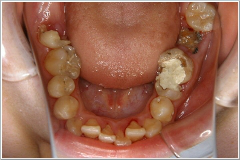

歯を磨く事を止めてしまった結果がここに出てしまったのです。

その写真をここに載せますので見て下さい

これがうら若き女性のお口の中です。 初めはからかうつもりのいじめだったかも知れませんが、それがエスカレートして、生きる入り口の口腔機能を破壊するに止まらず、未来多き乙女の身も心もズタズタにし、更にその家庭をも破壊したいじめを私は決して許す事は出来ません。Eさんは当クリニックに3回通院してくれましたが、その後は体調不良を理由に通院は切れてしまいました。 本来であれば、約十本の抜歯、約十本の神経の治療を経て、約一年の歯科治療が必要と予測を立てていました。Eさんの予約は本人の希望で、他の患者さんとかち合わない様に、土曜日の午後にしていたのですが、3回通うのが精一杯だったのかも知れません。通院不可能で歯磨き不能あれば、せめて洗口するか、指にガーゼを巻いてプラークを拭い取るぐらいはして戴きたいと思いました。通院拒否という現実に、己の無力さを嘆きつつ、ソーシャルワーカーさんに何とか説得してもらう様頼むのが精一杯でした。私たちが空気の様に当たり前と思っている“日常”が壊されていく恐ろしさと、また日常を生きている有り難さを痛感させられた症例でした。